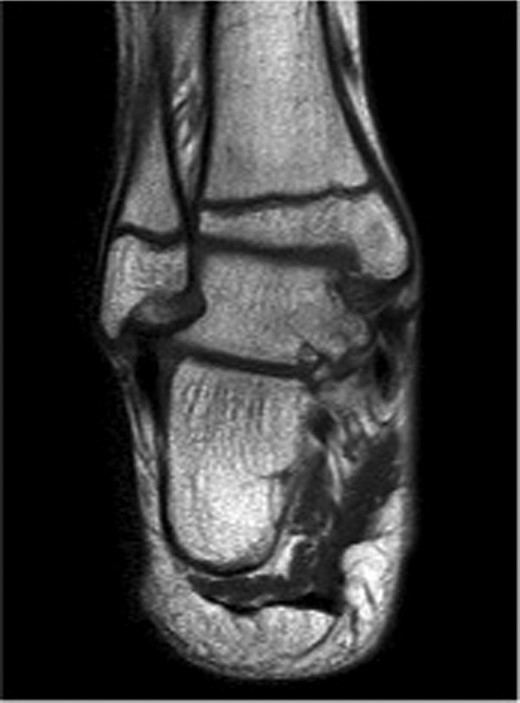

The patient subsequently underwent a manipulation under anaesthesia and POP application of his left distal tibia and right ankle to correct the talar displacement. Despite this, post-operative radiographs of the right ankle showed persistent widened medial tibio-talar joint, and the patient developed considerable right ankle pain and soft tissue swelling which did not correspond with the initial radiograph findings. Magnetic resonance imaging (MRI) of the right ankle joint was performed which revealed extensive marrow oedema through the medial malleolus epiphysis and the medial body of the talus. There was evidence of disruption of the medial cortex of the talus which explained the widened medial tibio-talar joint (Fig. 2). No disruptions of the epiphyseal plates or ligamentous structures were identified. The injury around the tibio-talar joint was identified as an undisplaced fracture through the postero-medial talus with a corresponding ‘kissing’-type lesion of the inner surface of the medial malleolus with gross soft tissue oedema. In view of the overlooked skeletal injury, a further computer tomography (CT) scan of the ankle joint was performed which confirmed a fragmented undisplaced fracture of the postero-medial aspect of the talus, with the anterior subtalar joint remaining intact and an undisplaced fracture through the medial malleolus (Fig. 3).

Right ankle MRI coronal view demonstrating bone marrow oedema in the medial malleolus and medial body of talus.